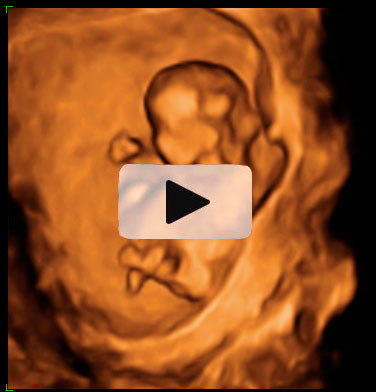

En la ecografía en 3D del feto en la 15ª semana de gestación se aprecia su anatomía. Es casi como la de un bebé a punto de nacer. Mide alrededor de los 10 cm y pesa unos 50 gramos.

Imagen de un feto de 15 semanas en ecografía 3D

La imagen es impresionante: la apariencia de este feto, de 15 semanas, es la de un niño que no le queda mucho tiempo de gestación para nacer. Cabeza, tronco, brazos y piernas se perfilan perfectamente en la ecografía del primer trimestre. Se lleva la mano a la boca mientras descansa apoyado en la pared uterina, como es normal es esta edad gestacional. La mayoría de las madres no se imagina que los fetos están tan "acabados" con apenas cuatro meses de embarazo.